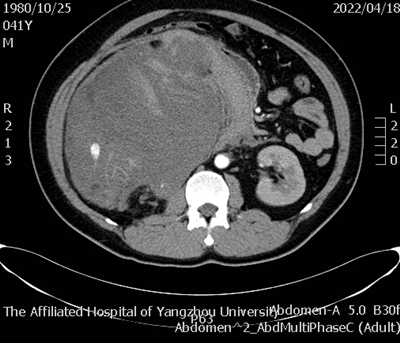

据悉,患者因“下腹部胀痛2天加重6小时”于西区医院外科急诊就医,经全腹部CT检查提示:右侧腹膜后巨大占位并破裂、出血,不除外肾脏或肾肿瘤破裂。据此情况,外科急诊遂收治泌尿外科进行救治。

王小祥表示,该患者右肾肿瘤的直径长达30cm实属罕见,对我院临床决策和手术技术提出了更高的要求和挑战。本次在我院多学科密切协助下患者得以术后快速康复,既是我院整体强大的急危重症处置能力的体现,也为我们今后处理类似病例提供了宝贵的经验。